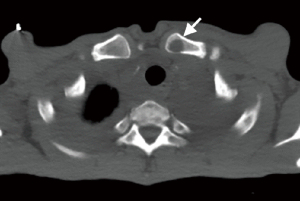

The involvement locations and incidence of bone lesions in 39 cases are detailed in Table 2. According to the morphology of bone lesions, these were divided into the following four types: (I) cystic changes (n=30; Figure 2), which showed single or multiple round-like cystic hypodense shadows in bone. The lesions had clear borders with or without sclerotic margins, and the maximum diameter was less than 5 cm. Marginal sclerotic margins (n=28), with one case showing iodized oil deposits within the lesion. (II) canal-like or honeycomb-like changes (n=34; Figure 3), which showed a tortuous, tubular distribution of hypointense shadow with clear margins and continuous at multiple levels above and below. The bone cortex was smooth or irregularly fractured in a worm-like pattern, while lesions were seen in 20 cases with iodized oil deposits. (III) Osteoporosis-like changes (n=16 cases; Figure 4), which showed a diffuse decrease in bone density and thinning of bone trabeculae. No lipiodol deposition was seen in any of the 16 cases in this group. (IV) Osteosclerosis-like changes (n=8; Figure 5), with two cases showing smooth thickening of the bone cortex, three cases showing increased density of osteophytes in the medullary cavity, three cases showing mixed presence, and five cases showing narrowing of the medullary cavity. Iodized oil deposition was not observed in any case.